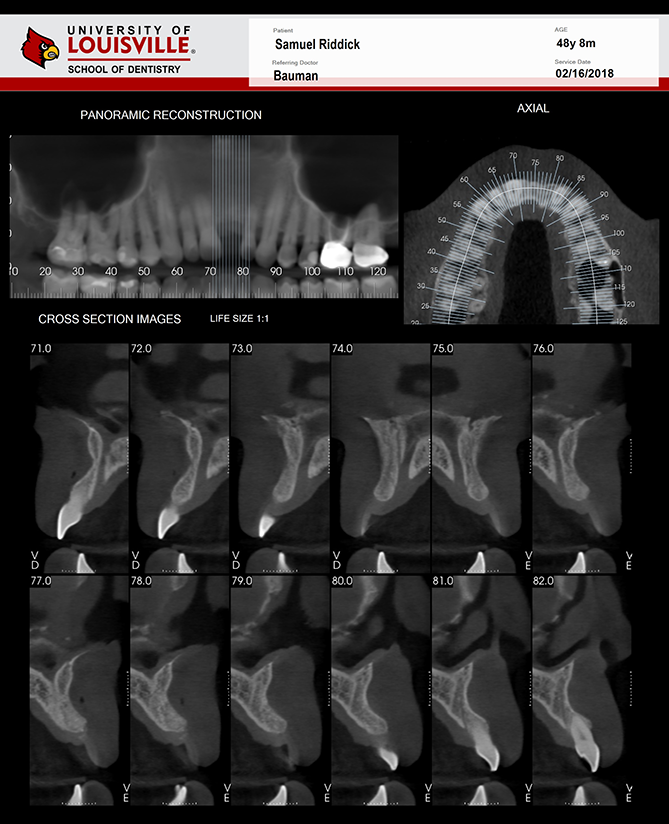

Este é um paciente masculino de 48 anos de idade e foi encaminhado para a clínica de Radiologia oral e maxilo-facial na Universidade de Louisville para uma aquisição de tomografia de feixe cônico da face para planejamento de implante.

Uma tomografia da maxila foi adquirida para avaliação do dente 21 e dos dois seios maxilares. Durante a interpretação do exame foi notado uma área ovalada, multilocular grande, bem definida, corticalizada na região retroclival prepontine. Este achado é fortemente consistente com Ecchordosis Physaliphora. Ecchordosis physaliphora é uma lesão hamartomatosa benigna congênita e pode ser encontrada em qualquer lugar da base do crânio ao osso sacrum. Também notei um forame jugular assimétrico no lado direito. Note que as margens são corticalizadas e não há sinais ou erosão / padrão mordida de traça. O aumento do forame jugular tornando-o assimétrico é fortemente consistente com Bulbo Jugular Alto. Esta variante anatômica ocorre mais comumente do lado direito. Há uma grande e fina espora óssea decorrente da parede lateral esquerda do septo nasal estendendo todo o caminho até a parede lateral esquerda da cavidade nasal.